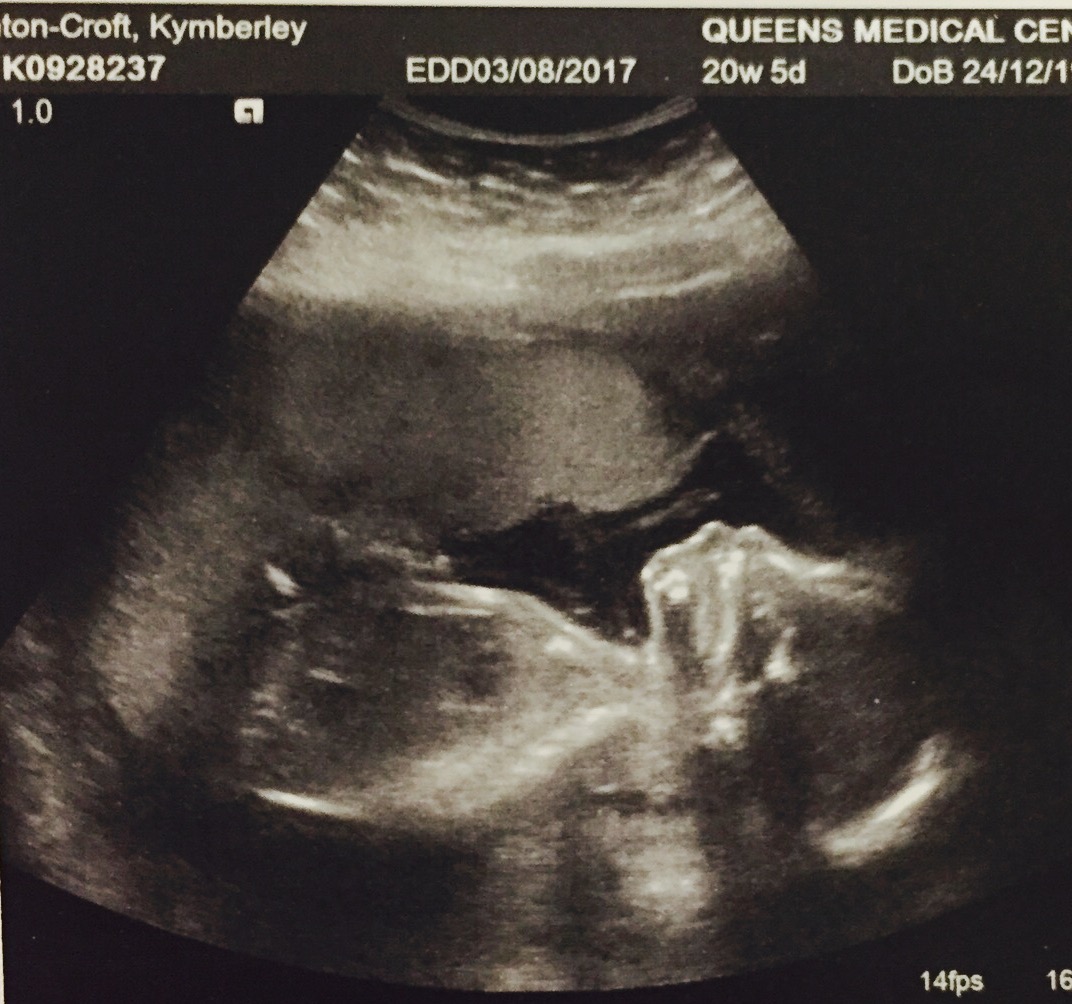

20+5 week scansAttachment 35790Attachment 35791Attachment 35792